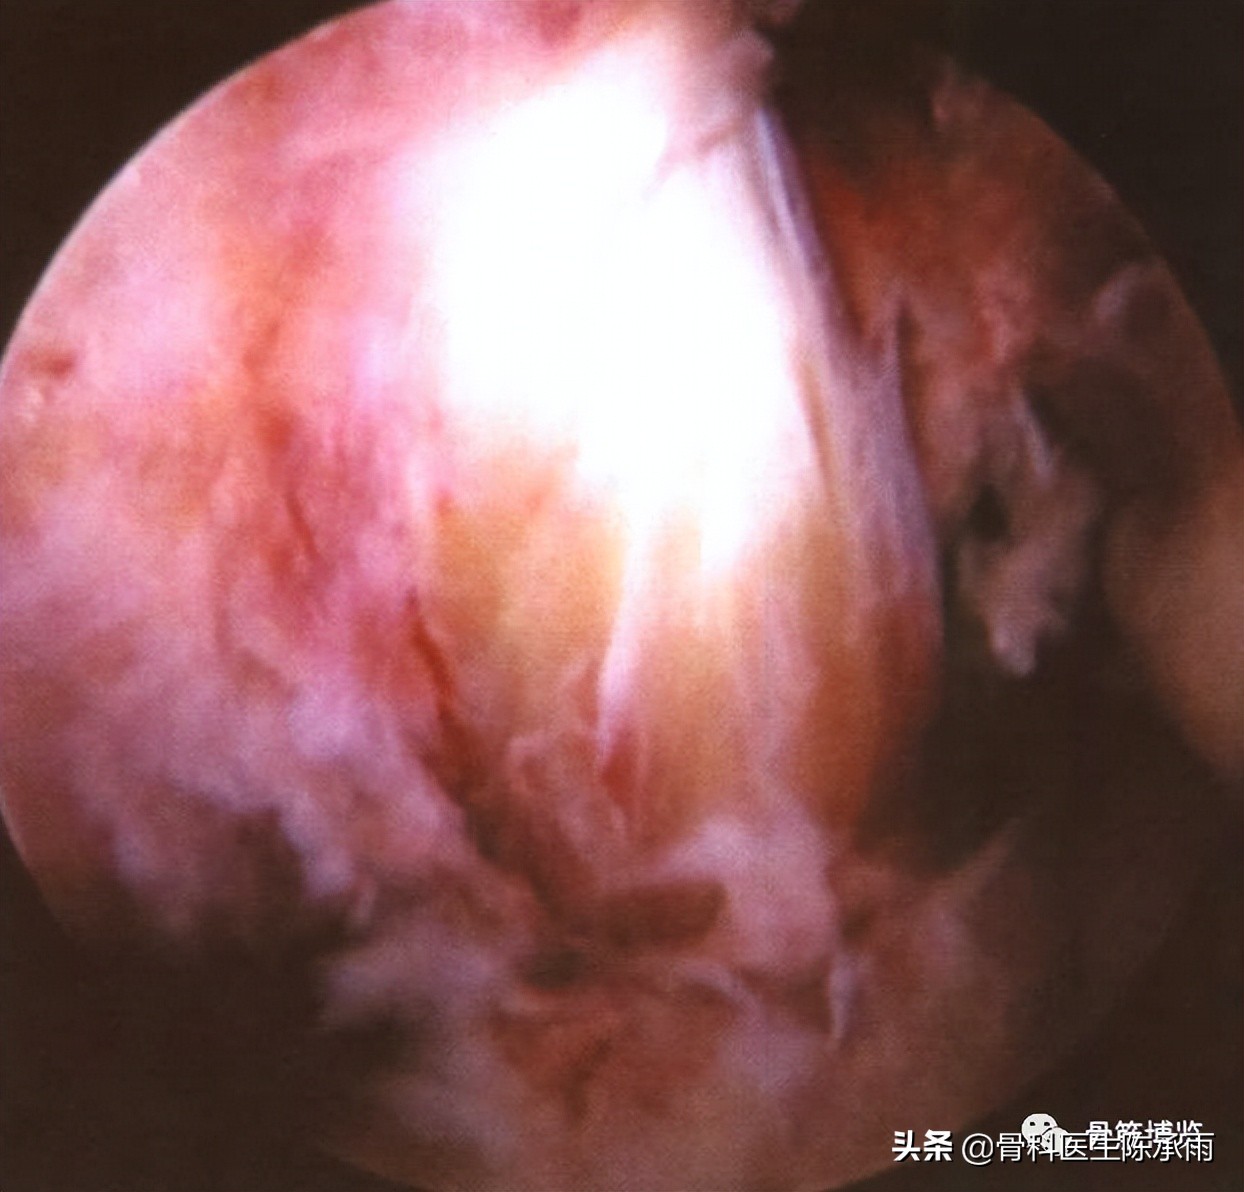

四、滑膜组织损伤

滑膜组织损伤多表现为充血、水肿、淤血,根据伤后时间不同而异,时间愈长,组织水肿愈明显。关节内韧带损伤时,其相应部位的滑膜组织改变更明显。因此,往往可根据局部滑膜的改变,进一步探查发现主要结构的损伤。

滑膜充血